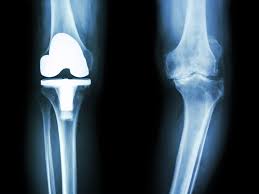

무릎 인공관절 수술, 왜 필요한가요?

무릎관절은 체중을 가장 많이 지탱하는 관절입니다. 나이가 들수록 연골은 점차 마모되고, 충격을 흡수하는 능력도 감소합니다. 이로 인해 통증, 뻣뻣함, 운동 제한이 생기며, 이런 증상이 악화되면 인공관절 수술이 필요해집니다.

퇴행성 관절염 외에도 류마티스 관절염이나 외상 후 관절 손상이 심각할 경우 수술이 권유되며, 수술을 통해 환자는 통증 없이 보행이 가능해지고 일상생활로 복귀할 수 있게 됩니다.